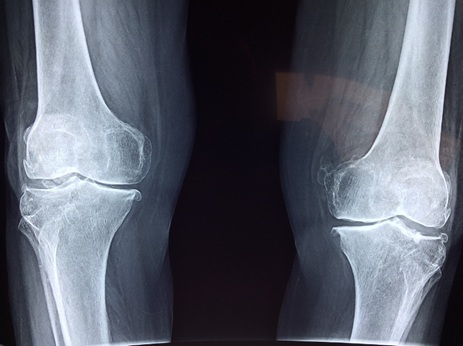

뼈는 살아 있는 조직입니다. 지속적인 자극을 받아야만 강도와 밀도를 유지할 수 있습니다. 운동은 뼈에 ‘기계적 하중(mechanical loading)’을 가함으로써 골세포(골아세포)를 자극하고, 뼈 형성 속도를 높입니다. 이는 골밀도(BMD, Bone Mineral Density)를 유지하거나 증가시키는 핵심 작용입니다. 유산소 운동이나 근력 운동을 하게 되면, 근육이 뼈를 당기고 누르면서 물리적 자극을 주게 됩니다. 이때 골막, 골세포, 골수 내에서 미세한 전기 신호가 발생하고, 이는 새로운 뼈조직의 형성을 촉진하는 생화학적 반응을 유도합니다. 또한 운동은 골흡수를 억제하고, 뼈 생성에 필요한 칼슘의 체내 이용률을 높이며, 비타민 D의 활성화를 촉진합니다. 체중을 실은 운동은 특히 효과적이며, 걷기, 계단 오르기, 가벼운 점프, 스쾃 등은 고관절, 척추, 무릎 등 주요 부위의 뼈 밀도를 증가시키는 데 유리합니다. 운동을 하지 않으면 뼈는 더 이상 자극을 받지 못하고 빠르게 밀도를 잃습니다. NASA 우주인들이 무중력 상태에서 골밀도가 감소하는 사례는 이를 입증하는 대표적 예입니다. 즉, 뼈 건강을 위해선 반드시 ‘중력+저항’을 동반한 운동이 필수적입니다.

골밀도를 높이기 위해선 단순한 유산소 운동보다는 체중 부하(weight-bearing) 운동과 저항성 근력 운동이 핵심입니다. 이는 뼈에 직접 자극을 주는 방식으로 뼈세포의 활성도를 높이고, 장기적으로 골밀도 유지에 크게 기여합니다. 가장 추천되는 운동은 다음과 같습니다: - 빠르게 걷기 또는 파워 워킹 (하루 30분 이상) - 스쾃, 런지 등 하체 중력 저항 운동 - 아령, 밴드, 체중을 활용한 상체 근력 운동 - 계단 오르기, 저 충격 점프 - 요가와 필라테스 (자세 정렬과 균형 유지에 효과) 주 3~5회, 한 번에 30~45분 운동이 권장되며, 일주일에 2~3회는 근력 중심으로 루틴을 구성하는 것이 바람직합니다. 운동 시 주요 관절과 뼈에 하중이 실리도록 하되, 관절염이나 기존 관절 문제가 있는 경우에는 전문가와 상의 후 프로그램을 조정하는 것이 필요합니다. 근육은 뼈를 움직이는 동력원이기 때문에, 근육량이 늘면 뼈에도 더 많은 자극이 전달됩니다. 특히 대퇴골, 고관절, 척추, 손목 부위는 골다공증과 골절 위험이 높은 부위이므로 해당 부위를 중심으로 한 운동이 중요합니다. 또한 유산소 운동과 병행할 경우, 심폐기능과 혈액순환이 개선되어 뼈에 영양소 공급이 원활해지고, 뼛속 미세 순환 구조가 유지되어 건강한 골조직 환경을 형성할 수 있습니다.